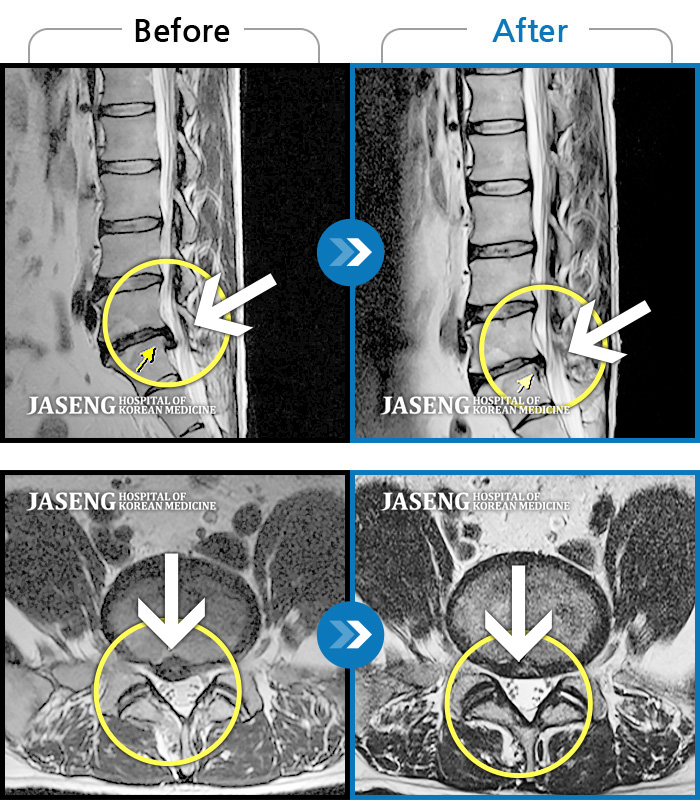

허리디스크

도움받은 사례

광주 · 장영우 원장

양측 허리부터 좌측 다리까지 이어지는 저림과 통증으로 걷기 힘들어 내원하였습니다.

촬영시기

2024.11.22 ~ 2025.05.16